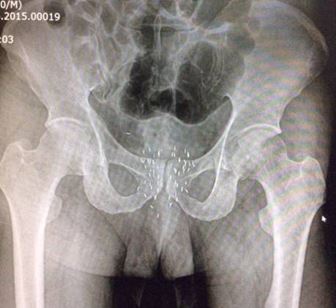

Tiến hành cấy hạt phóng xạ: 24 kim, tổng liều I-125: 145 Gy

• Sau thủ thuật:

• Soi bàng quang: không thấy tổn thương trong lòng bàng quang

• Rà phóng xạ: không có phóng xạ ở nước tiểu, môi trường

• Chụp XQ khung chậu thẳng: vị trí kim được cắm tốt

• Bệnh nhân tụ máu nhẹ tầng sinh môn